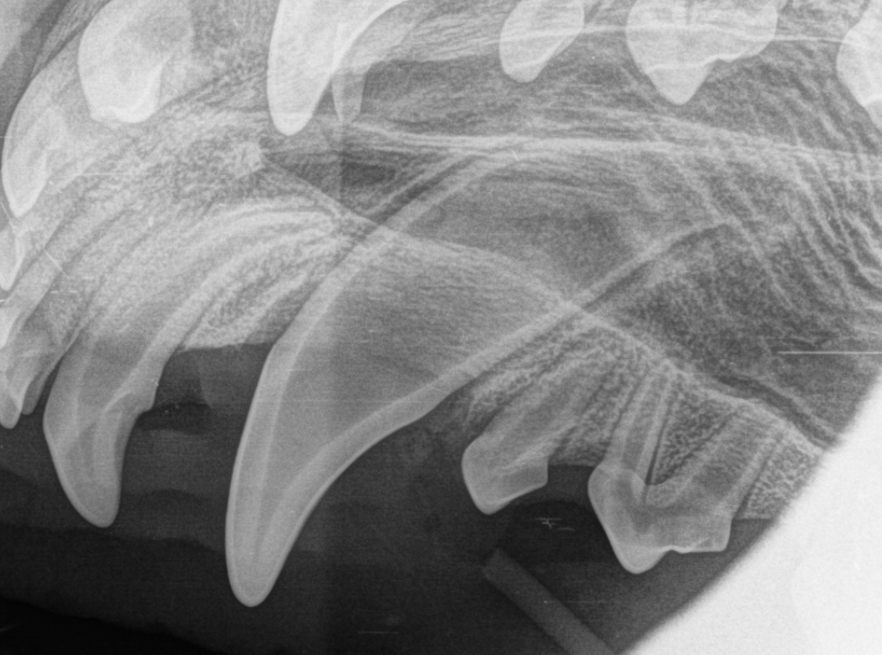

Vi tok røntgen både før og etter inngrepet for å sikre at alt var fjernet og at de permanente tennene ikke var skadet. Til slutt ble tannkjøttet sydd.

Hos Chicco satt melketennene helt fast og var ikke til å rikke. Siden han var seks måneder gammel, ble det besluttet å trekke dem.

Chicco ble lagt i full narkose og fikk både lokalbedøvelse og god smertelindring. Under inngrepet åpnet vi tannkjøttet og fjernet noe av tannbeinet for å få ut hele tannen med roten.